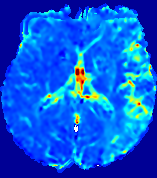

LesionRefer to captionRefer to captionRefer to captionRefer to captionRefer to captionRefer to caption𝐕rgbsubscript𝐕𝑟𝑔𝑏{\bf{V}}_{rgb}Refer to captionRefer to captionRefer to captionRefer to captionRefer to captionRefer to caption𝐕2subscriptnorm𝐕2{\|\bf{V}}\|_{2}Refer to captionRefer to captionRefer to captionRefer to captionRefer to captionRefer to captionRefer to caption3.53.53.52.82.82.82.12.12.11.41.41.40.70.70.70.00.00.0(mm/s)𝑚𝑚𝑠(mm/s)D𝐷DRefer to captionRefer to captionRefer to captionRefer to captionRefer to captionRefer to captionRefer to caption0.0200.0200.0200.0160.0160.0160.0120.0120.0120.0080.0080.0080.0040.0040.0040.0000.0000.000(mm2/s)𝑚superscript𝑚2𝑠(mm^{2}/s)Slice #1Slice #2Slice #3Slice #4Slice #5Slice #6

Figure 3: PIANO feature maps for one stroke patient, where the lesion is located in the left hemisphere. Top row: segmented stroke lesion region (white) on different slices, obtained from ISLES 2017. The corresponding slices for the PIANO feature maps are shown in the following rows.

For a better insight into an estimated velocity field 𝐕𝐕{\bf{V}} and diffusion field 𝐃𝐃{\bf{D}}, we compute the following maps: (1) 𝐕rgbsubscript𝐕𝑟𝑔𝑏{\bf{V}}_{rgb}: Color-coded orientation map of 𝐕=(Vx,Vy,Vz)T𝐕superscriptsuperscript𝑉𝑥superscript𝑉𝑦superscript𝑉𝑧𝑇{\bf{V}}=(V^{x},V^{y},V^{z})^{T}, obtained by normalizing 𝐕𝐕{\bf{V}} to unit length and mapping its 3 components to red, green, blue respectively; (2) 𝐕2subscriptnorm𝐕2\|{\bf{V}}\|_{2}: 222 norm of 𝐕𝐕{\bf{V}}; (3) D𝐷D: scalar field in Eq. 5.

Fig. 3 and Fig. 4 show the PIANO feature maps estimated from two ISLES 2017 patients: all are highly consistent with the lesion in both cases. Details of the blood flow trajectories are revealed in 𝐕rgbsubscript𝐕𝑟𝑔𝑏{\bf{V}}_{rgb} by the ridged patterns and the sharp changes of colors in the unaffected (right) hemisphere, while the flat patterns appearing within the lesion provide little directional information about the velocity and indicate low velocity magnitudes. Velocity magnitudes are more directly visualized via 𝐕2subscriptnorm𝐕2\|{\bf{V}}\|_{2}, from which one can easily locate the lesion where 𝐕2subscriptnorm𝐕2\|{\bf{V}}\|_{2} is low. D𝐷D also indicates lower diffusion values in the lesion, though with less contrast potentially due to the fact that it captures the accumulated effect of CA diffusion at the voxel-level.